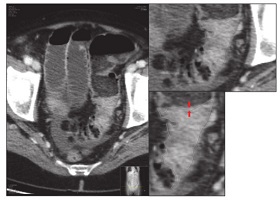

For most people, talking about the digitization of diagnosis by images may seem a little far, but the truth is that we are dealing with an important issue that affects decisively the health care of the majority of the people. Namely, in any city, without it being necessary to visit the large capitals, there are in each hospital several scanners of computed tomography, magnetic resonances, ultrasounds, telemedicine…. A multitude of new equipment has emerged in unprecedented growth, unless we go back to the time immediately after the discovery of X-rays in 1895.

Digitization of both the radiologic images and the clinical and demographic data provides an increase in the quality of health care and procedures. Digitization strategy in the health environment rests on two strength ideas: the logical integration of the image data (PACS) with the clinical and demographic data of the patient; and the transmission of data and images. The advantages of the digital format (processing, reconstruction of the images in the different planes of the space, in three dimensions and video (4D), transmission to remote places and through the network of the medical images accompanied by the pertinent information of the patients, etc), explain the primacy of the process.

It is impossible to know. But we may venture to point out three innovations with character, and potentially transformative. One is in the field of archiving and communications, where there will be interesting news related to storage and also to the improvement in the speed of transmission and recovery of images, as well as technologies at lower costs. The second is the increasing interconnection of all types of devices and objects through the Network. Medical reports can be written in a support (tablet, telephone...) that will not necessarily have to be located in either a hospital or other health center. A third group of innovations will be related to technologies that may improve diagnosis and treatment, either by lowering the price of medical services themselves, by helping people with disabilities, by improving the quality of life of the elderly, or by developing algorithms for computer-aided diagnosis and quantitative extraction of imaging features from medical scans (“Radiomics”).